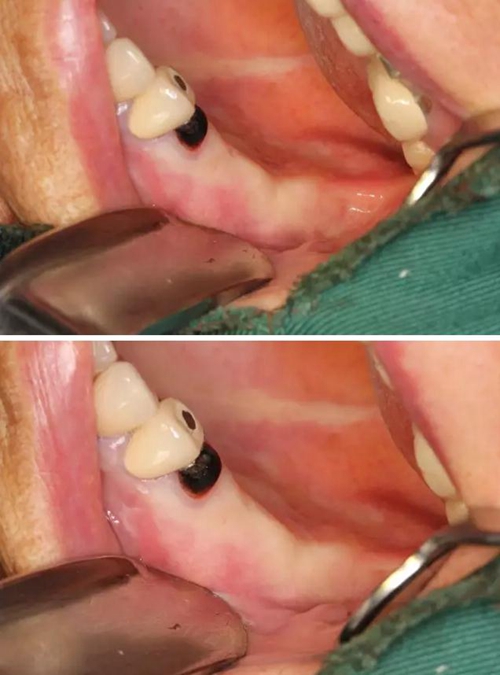

【病例分享】右上內(nèi)提+5冠延長(zhǎng)1 梁光強(qiáng)